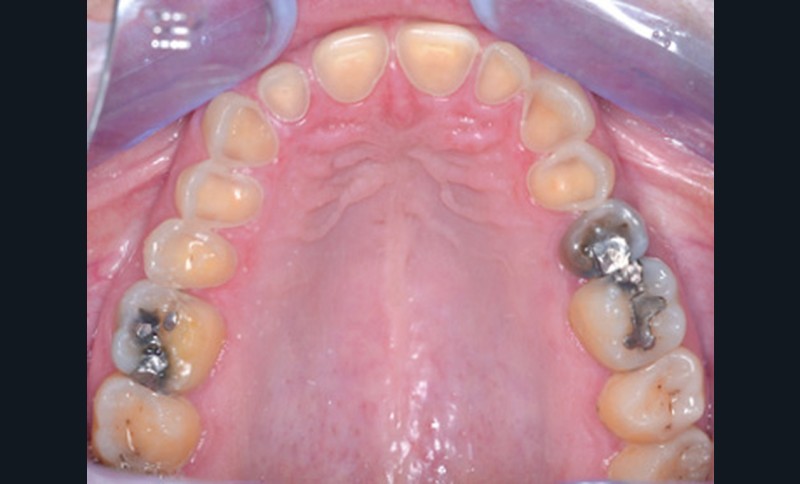

Mme V. est adressée au cabinet dentaire pour une réhabilitation de son sourire. À l’examen clinique, elle présente des usures sur l’ensemble de son maxillaire (fig. 17 et 18). Après évaluation du décalage OIM-ORC, une position de référence en relation centrée avec une dimension verticale augmentée est enregistrée. Pour valider cette position, il est demandé au laboratoire de réaliser un wax-up virtuel. Ce dernier est validé puis transféré en bouche pour essayage (fig. 19 et 20).